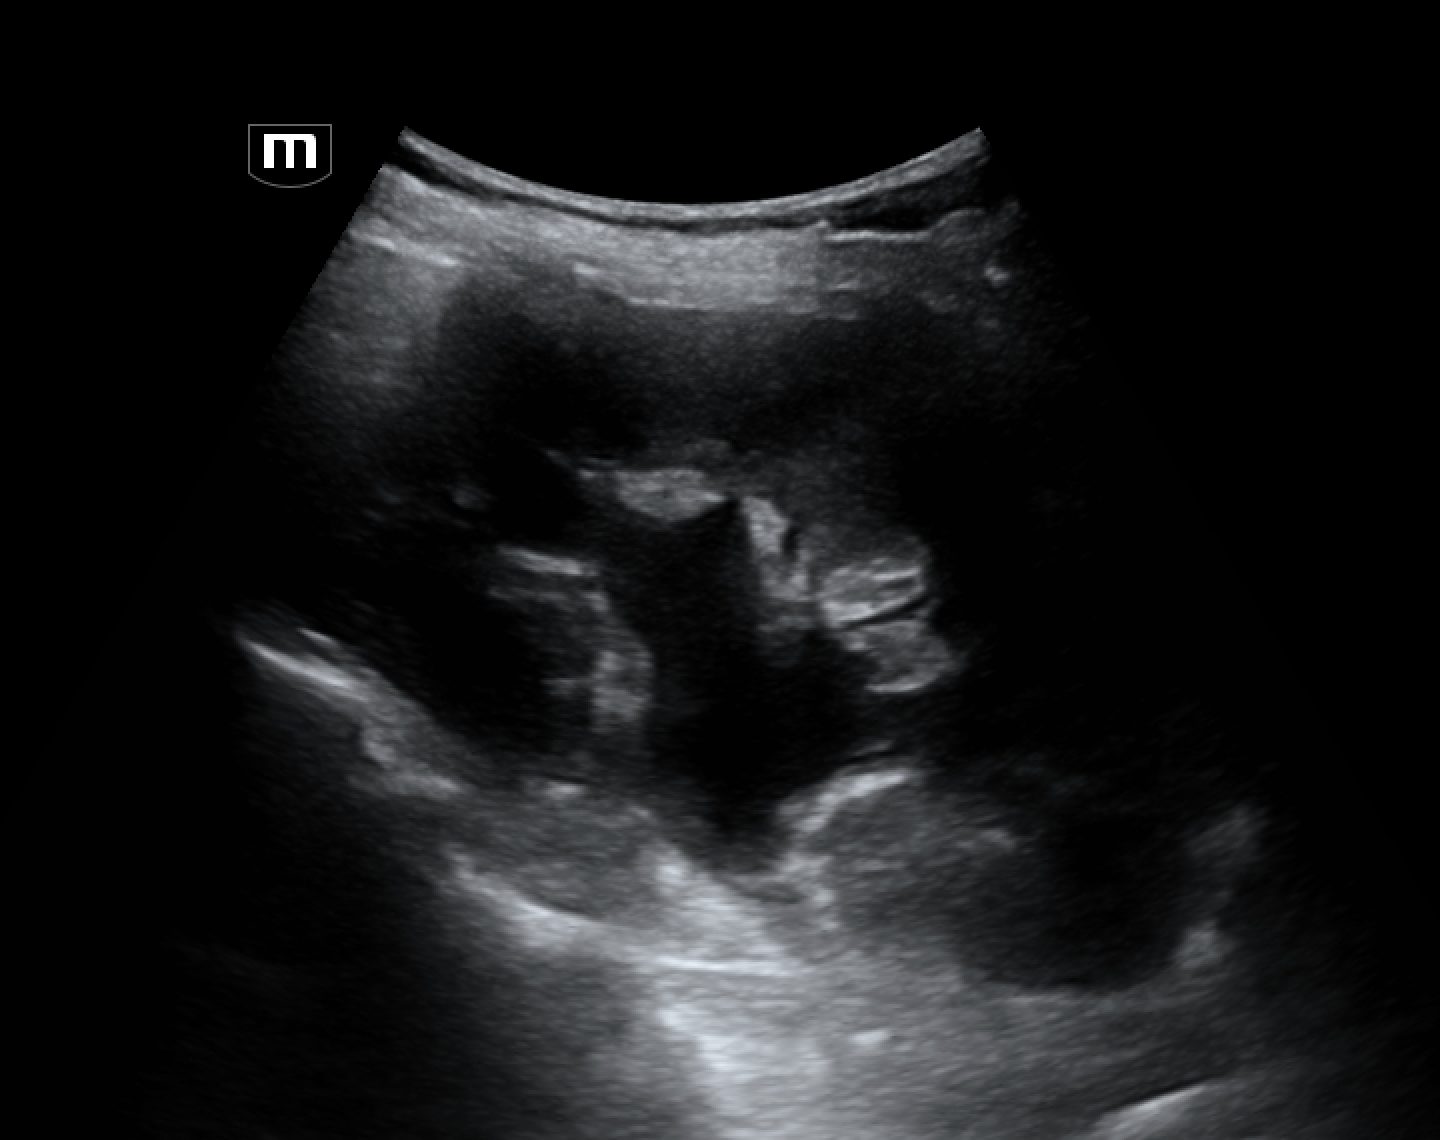

Bedside US was negative for pelvic free fluid of masses. However, renal US revealed:

R kidney (long)

This image shows grade 2 hydronephrosis: dilated renal pelvis and ureter and distended calyces. But notice the renal cortex is normal thickness. Also the calyces do not look clubbed, they maintain their normal branching structure. The left kidney was normal.

Grades of hydronephrosis: Grade 1: dilated pelvis and ureter only; Grade 2: + dilated calyces, but not clubbed; Grade 3: + clubbed cayces but normal cortical thickness >1cm; Grade 4: + thin cortex

The degree of hydronephrosis isn't always a reliable indicator of the degree of obstruction because it is also determined by the duration of obstruction and the degree of hydration. But typically, significant obstruction leads to higher grade hydronephrosis.